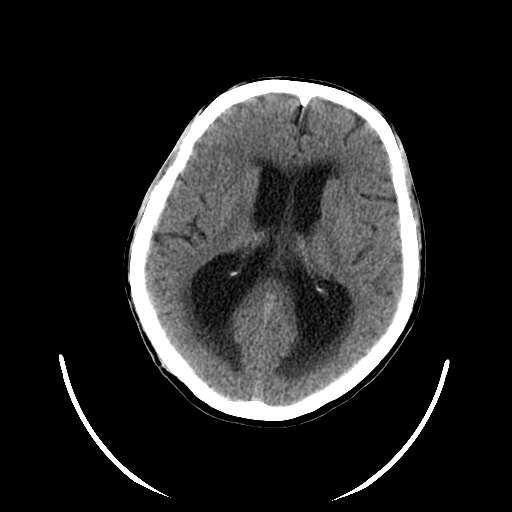

以下是引用hhcckk在2007-10-9 10:03:00的发言:[br]galen';s静脉瘤又称大脑大静脉瘤,是由于动静脉短路,大量血流进入galen';s静脉(大脑大静脉),造成该静脉瘤样扩张所致,病理上典型的galen';s静脉瘤包括一明显扩张的囊状galen';s静脉和引流galen';s静脉的短路血管,,这些短路血管多来源于颈内动脉系统或基底动脉系统,多异常扩大、迂曲。巨大的galen';s静脉瘤可造成中脑压迫,导水管闭塞,引起梗阻性脑积水。[br]galen';s静脉瘤ct表现较典型,根据其部位、形态、增强前后表现及脑积水表现较易诊断。[br]支持张主任,此病人病灶强化明显,正常松果体增强后在病灶的后方可见,可以再做个mr,血管性的病灶在mr上有流空效应,增强后明显强化,诊断更有把握